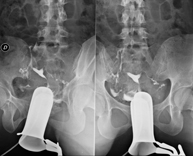

- Voiding Cystourethrography (VCUG)

Serial voiding cystourethrography involves radiological imaging to assess the anatomy and function of the urethra and bladder with the administration of iodinated contrast through a bladder catheter.

- Urethrocystography (Urethro-CG)

Retrograde-minctional urethrocystrography involves radiological imaging to assess the anatomy and function of the bladder and urethra. Contrast material is applied through a small catheter placed in the urethra and images are obtained during the filling and emptying of the bladder.